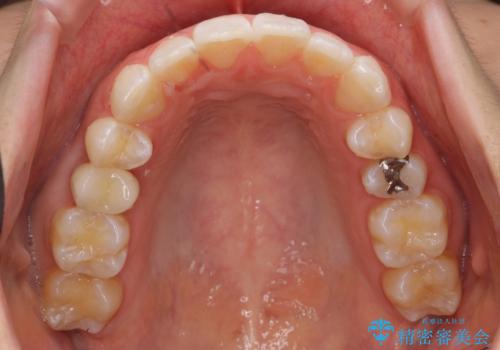

- 前歯のがたつきを治したいとのことでした。歯を抜かずにできる範囲で引っ込めたいとのことでした。

歯列の側方拡大(横に広げる)と、エナメル質の削合で並べました。

右上4番目の被せ物の治療については以下で紹介しています。